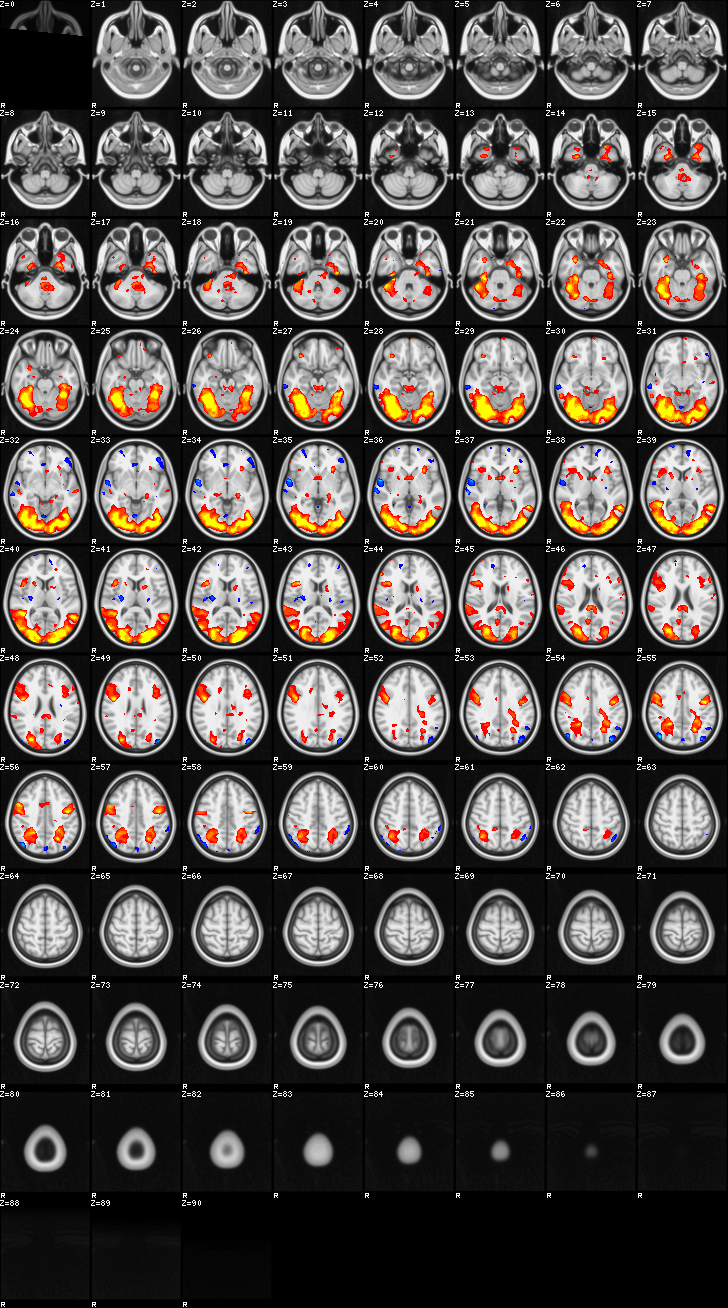

Mixed Effect (flame1)¶

ATM it is 8 subjects, 8 mm FWHM spatial smoothing, preliminary results only

Images thresholded abs value > 2.3 and colormap goes from 2.3 to 5 (red->yellow) or -2.3 to -5 (blue->lightblue)

03-self¶